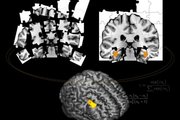

Study participants were at least 60 years old and were free of dementia and stroke. The evaluation included total cerebral brain volume, a marker of age-associated brain atrophy; hippocampal volume, which reflect changes in the area of the brain that controls memory; white matter hyperintensity volume, which can be used as a measure of pathology and aging; and covert brain infarcts.

The study found that an increase of only 2µg per cubic meter in PM2.5, a range commonly observed across metropolitan regions in New England and New York, was associated with being more likely to have covert brain infarcts and smaller cerebral brain volume, equivalent to approximately one year of brain aging.

"This study shows that for a 2 microgram per cubic meter of air (μg/m3) increase in PM2.5, a range commonly observed across major US cities, on average participants who lived in more polluted areas had the brain volume of someone a year older than participants who lived in less polluted areas. They also had a 46 percent higher risk of silent strokes on MRI," said Sudha Seshadri, MD, a Professor of Neurology at Boston University School of Medicine and Senior Investigator, the Framingham Study.